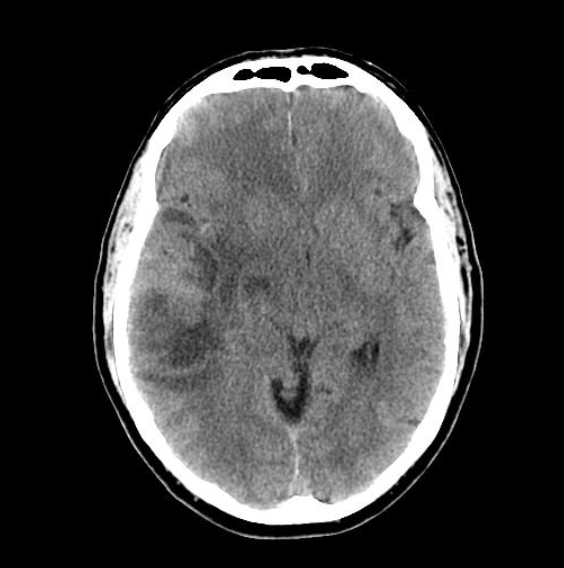

Hvilken type scanning? Diagnose? (Hvis du ofrer 200 point kan tilvælges et ekstra af følgende scanningsbilleder: CT med kontrast, MR T1-vægtet, MR T2-vægtet)

Glioblastom